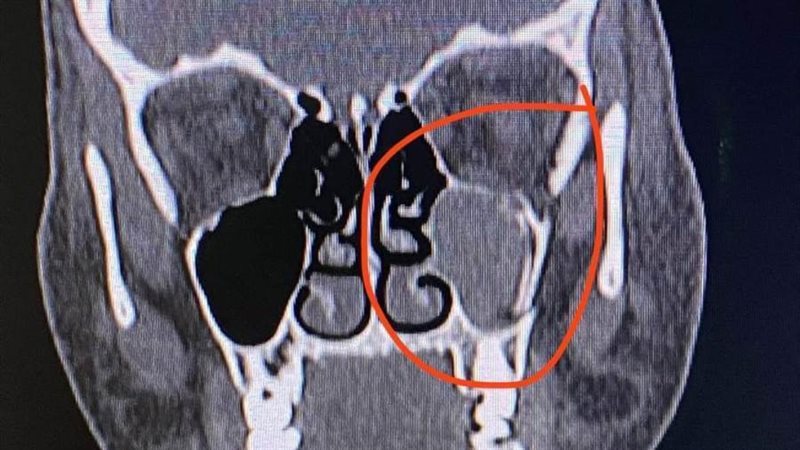

وتمكن الفريق الطبي بقسم "جراحة الوجه والفكين والتجميل" تحت إشراف مدير المستشفى واستشاري جراحات التجميل الدكتور أحمد حمدي خضر أخصائي جراحة الوجه والفكين والدكتور محمد جلال الديب وبمساعدة الدكتور ضياء ياسين من إصلاح عدة كسور منها كسر بالوجه وكسر مجمع في عظم قاع العين وعظم الخد باستخدام جرح تجميلي داخل جفن العين "Transconjunctival approach" وتثبيت الكسر بشرائح صغيرة من دون إحداث جروح خارجية بالوجه.